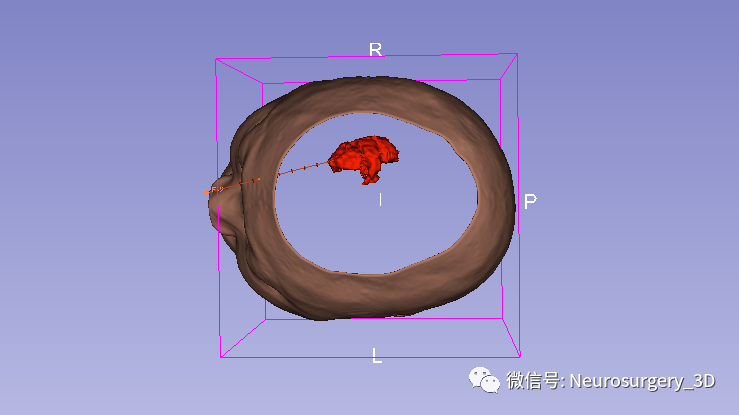

2、可透视化显示颅内血肿形态

放大后不同视角观察

透视化血肿状态下显示穿刺路径走形在血肿中心